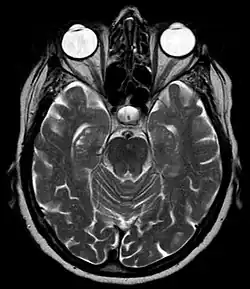

![]() Hippocampal sulcus labeled at center. | |

The hippocampal sulcus, also known as the hippocampal fissure, is a sulcus that separates the dentate gyrus from the subiculum and the CA1 field in the hippocampus.

During human fetal development, the hippocampal sulcus first appears at approximately 10 weeks of gestational age. At this stage it exists as a broad shallow fissure along the surface of the dentate gyrus. Gradually, the fissure deepens and shifts toward the cornu ammonis. After about 18 weeks, the walls of the fissure fold into each other and begin to fuse. By 30 weeks, the hippocampal sulcus is normally obliterated except for its most medial part, leaving a shallow surface indentation.[1]

Enlargement of the hippocampal sulcus has been associated with medial temporal lobe atrophy occurring in Alzheimer's disease.[2]